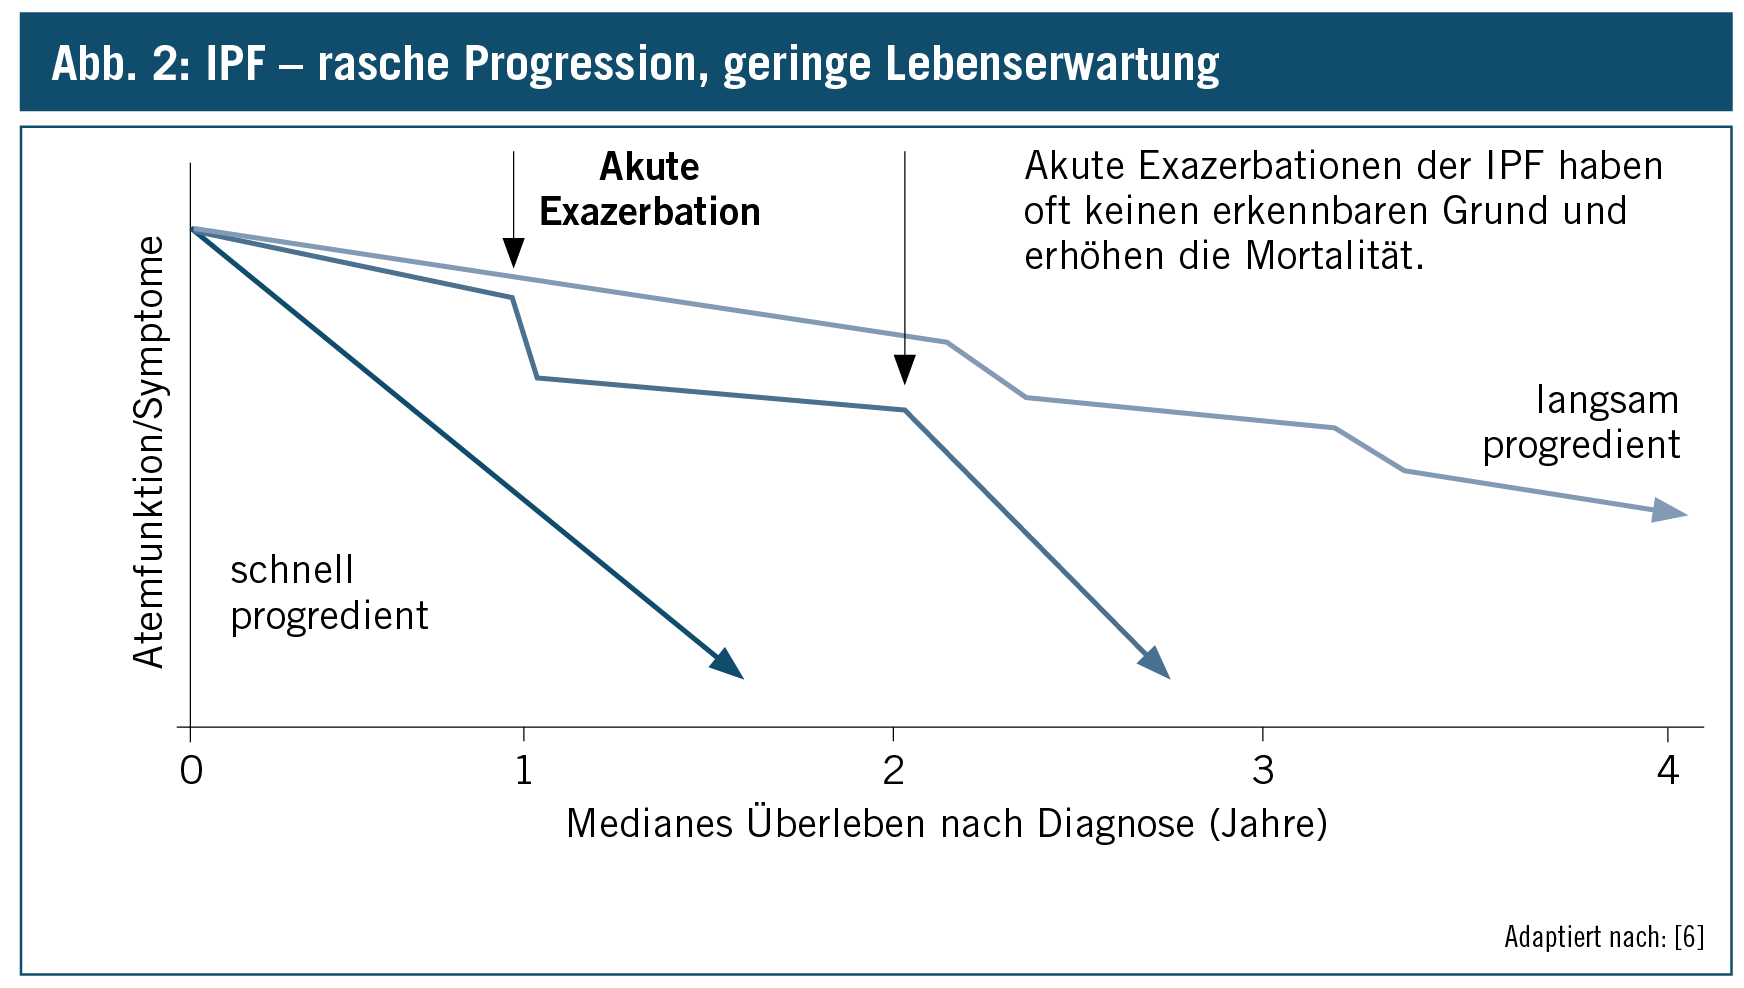

Eine Lungenfibrose kann verschiedenste Ursachen haben, als Entzündungsauslöser kommen beispielsweise Schadstoffe in der Atemluft, chronische Infektionen, Systemerkrankungen wie die Sarkoidose sowie bestimmte Medikamente in Frage. Auch bei einigen chronisch entzündlichen rheumatischen Erkrankungen kann eine Fibrose auftreten. Bei gut der Hälfte der Patienten lässt sich die Erkrankung allerdings auf keinen Auslöser zurückführen, die Ursache bleibt nicht bekannt. Man spricht dann von einer idiopathischen interstitiellen Lungenfibrose. Diese wird wiederum in verschiedene Unterformen unterteilt, die verbreitetste Form ist die idiopathische pulmonale Fibrose, kurz IPF. Sie ist zugleich die Form der Fibrose mit dem ungünstigsten Verlauf. Die aktuelle Forschung konzentriert sich auf diese, noch nicht ursächlich behandelbare Unterform der Lungenfibrose. Erfahren Sie hier mehr zur aktuellen Forschung.

Nach derzeitigem Stand von Medizin und Forschung ist eine Lungenfibrose nicht heilbar. Ziel der Fibrose-Therapie ist es deshalb, das Fortschreiten der Vernarbung zu stoppen, beziehungsweise zu verlangsamen. Einmal bestehende Vernarbungen des Lungengerüsts lassen sich nicht mehr rückgängig machen. Durch eine symptomatische Therapie lassen sich darüber hinaus die als äußerst belastend empfundenen Beschwerden, die mit einer Fibrose einhergehen, lindern. Dazu gehören die Gabe von bronchienerweiternden Medikamenten (Anticholinergika, Beta-2-Sympathometika als Dosiersprays, Theophyllinpräparate in Tablettenform), wodurch sich auch die Selbstreinigung der Schleimhäute verbessert. Auch eine Sauerstofflangzeittherapie verbessert die körperliche Leistungsfähigkeit, so dass die Betroffenen wieder in der Lage sind, ihren Alltag unabhängig und selbständig zu bewältigen.

Da fibrosierende Lungenerkrankungen oft eine entzündliche Komponente aufweisen, ist die Gabe von Cortison-Präparaten ein wichtiges Element der Medikation (Corticosteroide, Gluccocorticoide oder, kurz, Steroide). Die synthetischen Abkömmlinge des körpereigenen Cortisols wirken anti-entzündlich und anti-allergisch. Darreichungsformen sind Spritzen oder Tabletten, zudem sind sie auch als Inhalat anwendbar. Ist die Lungenfibrose die Folge einer rheumatischen Grunderkrankung, kommen bei der Therapie zusätzlich Immunsuppressiva zum Einsatz, die das Immunsystem dämpfen und so Entzündungsprozesse hemmen. Bei der häufigsten Form der Fibrose, der idiopathischen pulmunalen Fibrose (IPF) werden sowohl Immunsuppressiva als auch Cortisonpräparate eingesetzt, allerdings spricht die Krankheit nur selten darauf an und wenn, dann meist nur vorübergehend. Dies liegt vor allem daran, dass mit der IPF selten eine entzündliche Komponente einhergeht.

Lange galt die IPF als unbehandelbar, es gab keine medikamentöse Therapie, mit der sich der Verlauf verzögern oder gar stoppen ließ. Seit einigen Jahren sind zwei Medikamente zur Behandlung von IPF zugelassen: Pirfendion und Nintedanib. Beide Medikamente verhindern die Bildung von Kollagenfibrillen. Konkret heißt das, sie vermindern zum einen die Entstehung von Kollagenmolekülen und sorgen zum zweiten dafür, dass die vorhandenen Kollagenmoleküle sich zu größeren Verbänden, den so genannten Kollagenfibrillen, zusammenlagern. Mehr zur aktuellen Forschung und Studienlage lesen Sie hier. Im Endstadium der Erkrankung, wenn die Lungenfunktion derart eingeschränkt ist, dass nahezu kein Gasaustausch in der Lunge mehr stattfinden kann, kann eine Lungentransplantation oftmals die letzte Möglichkeit sein, die Mortalitätsrate sinkt dadurch signifikant. Über die Aufnahme eines Patienten in die Warteliste, ihre Führung sowie über die Abmeldung entscheidet eine ständige, interdisziplinäre und organspezifische Transplantationskonferenz des Transplantationszentrums. Mindestens ein Mediziner, der nicht unmittelbar in das Transplantationsgeschehen eingebunden ist, nimmt an dieser Konferenz teil. Grundlage für die Vermittlung von Lungen ist der so gennannte Lung-Allocation-Score (LAS). Der LAS ermittelt mit Hilfe von geeigneten Kenndaten des Patienten